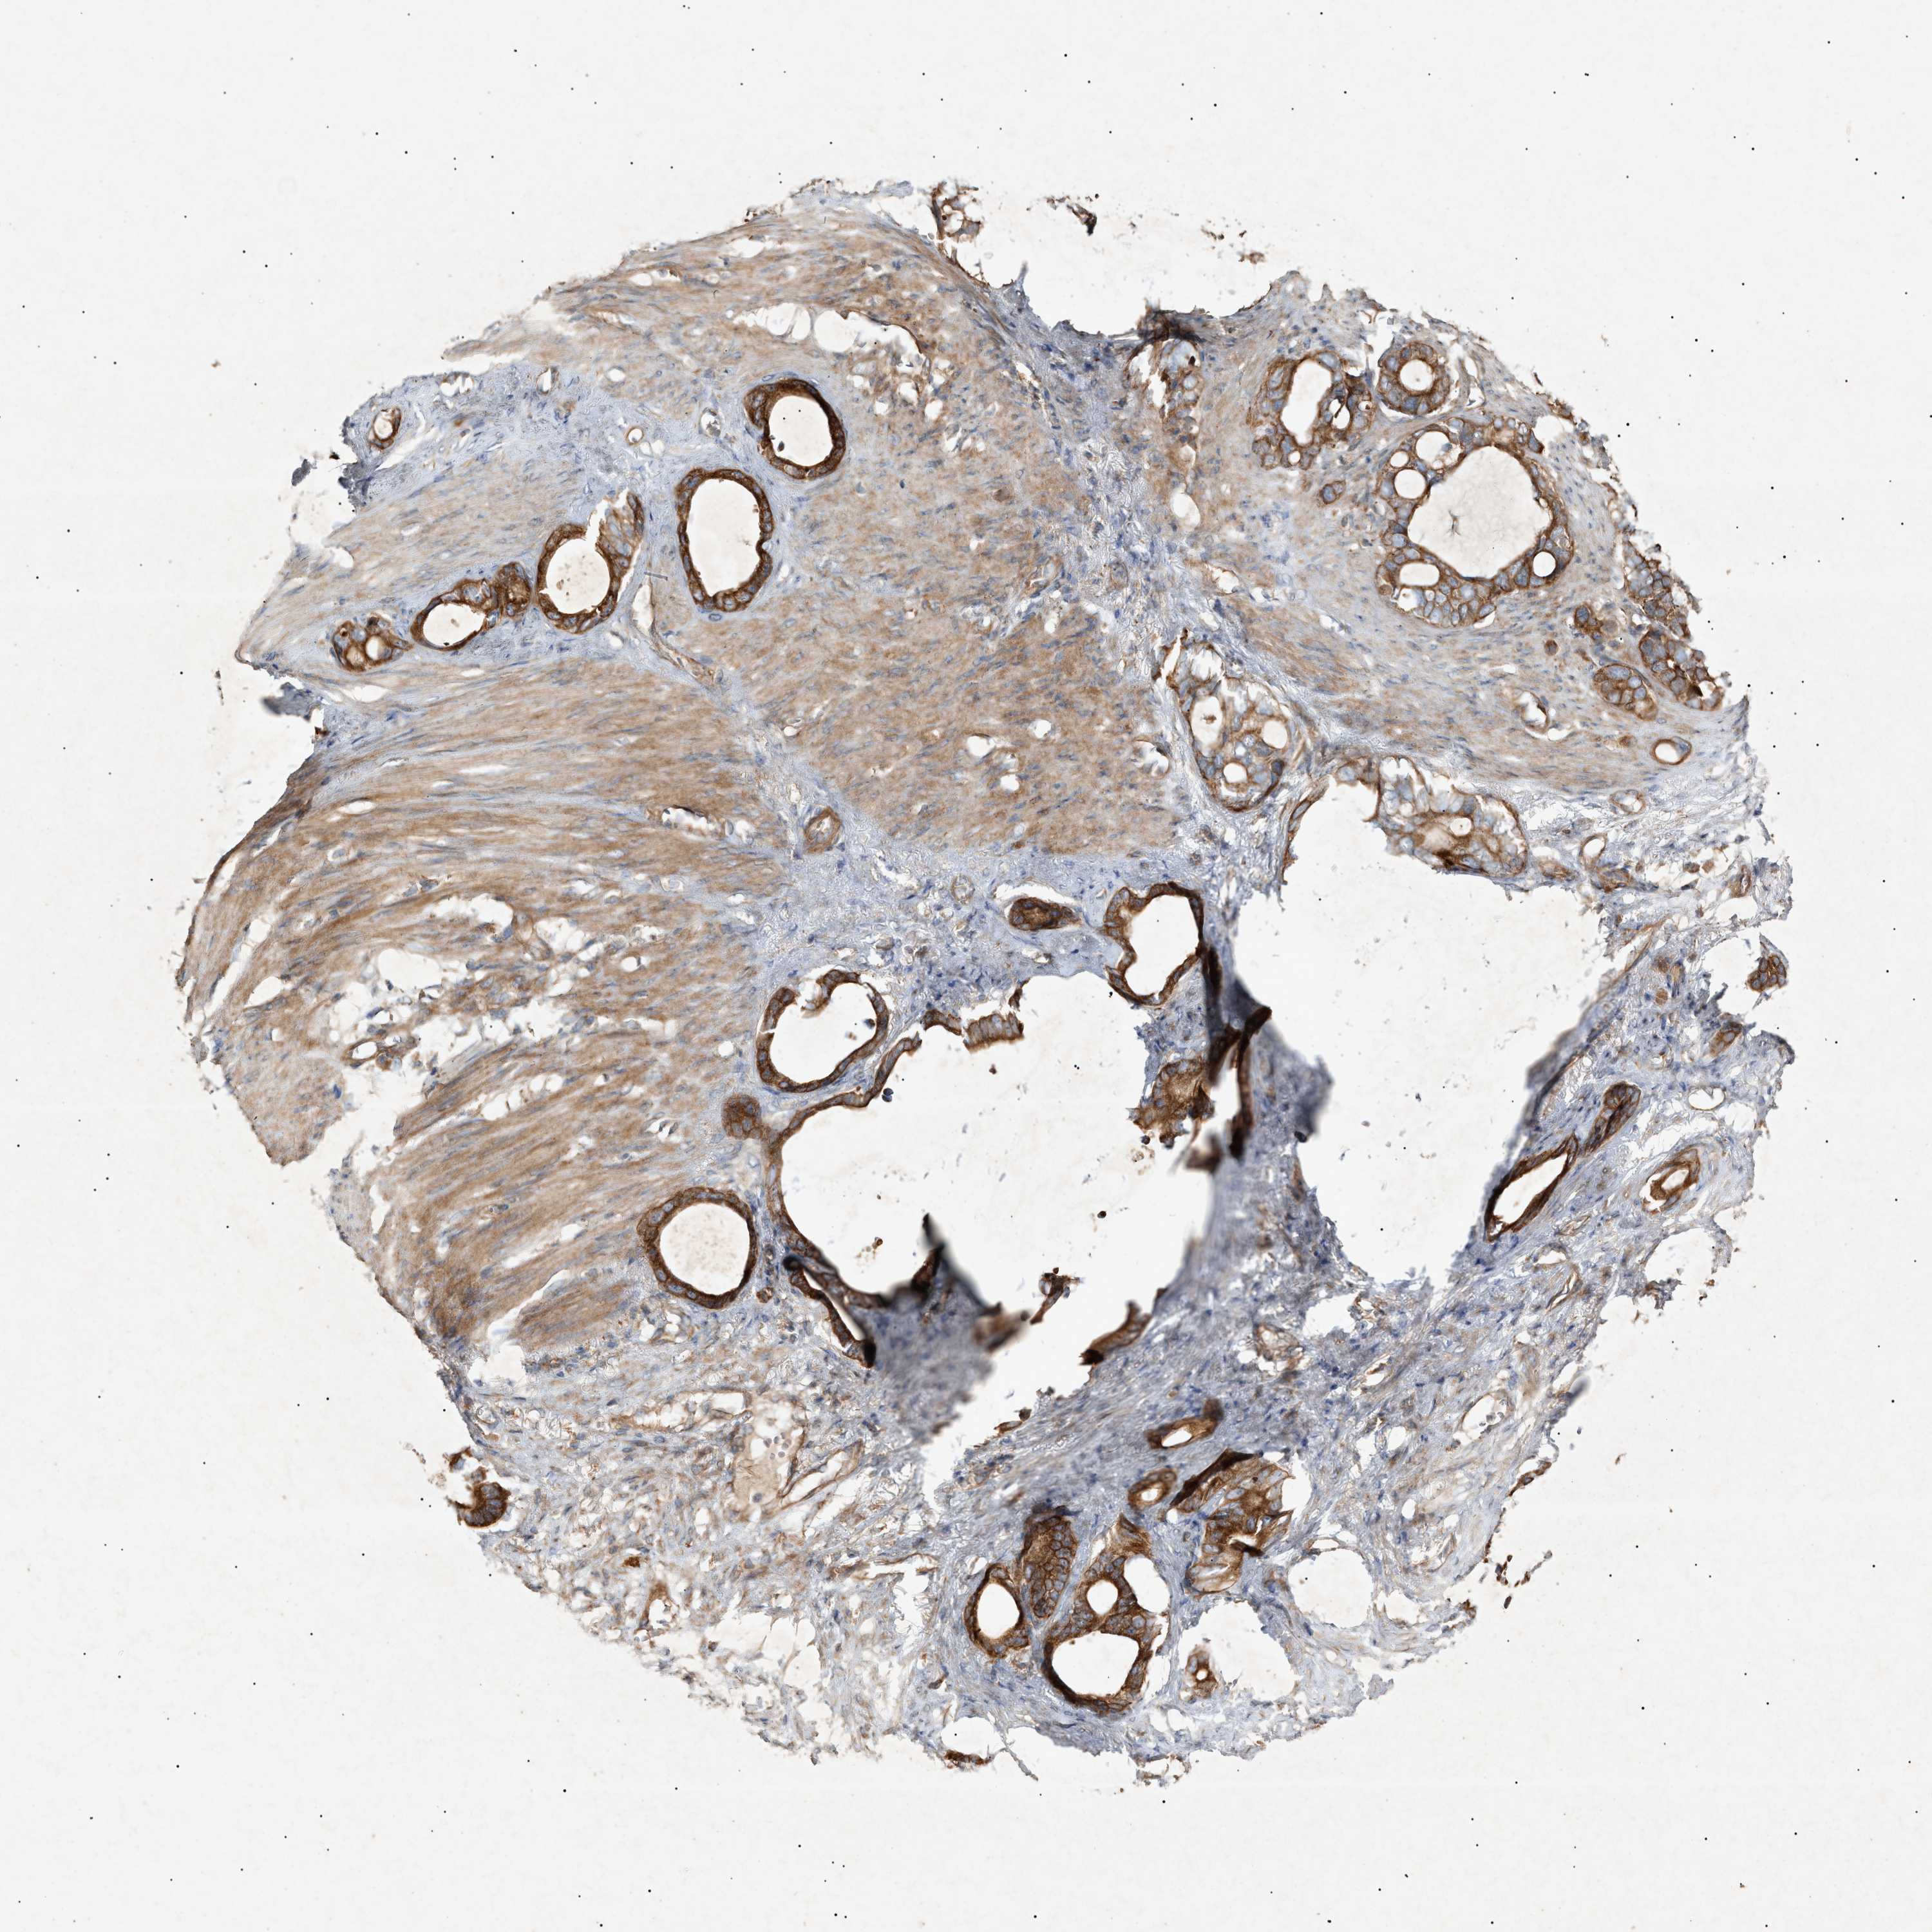

STOMACH CANCER - Protein expressioni

A mouse-over function shows sample information and annotation data. Click on an image to view it in a full screen mode. Samples can be filtered based on level of antibody staining by selecting one or several of the following categories: high, medium, low and not detected. The assay and annotation is described here.

Note that samples used for immunohistochemistry by the Human Protein Atlas do not correspond to samples in the TCGA dataset.

Antibody stainingi

Antibody staining in the annotated cell types in the current human tissue is reported as not detected, low, medium, or high, based on conventional immunohistochemistry profiling in selected tissues. This score is based on the combination of the staining intensity and fraction of stained cells.

Each image is clickable and will lead to virtual microscopy that enables deeper exploration of all samples and also displays staining intensity scores, fraction scores and subcellular localization as well as patient and tissue information for each sample.

Antibody HPA015971

Staining

High

Medium

Low

Not detected

Intensity

Strong

Moderate

Weak

Negative

Quantity

>75%

75%-25%

<25%

None

Location

Nuclear

Cytoplasmic/membranous

Cytoplasmic/membranous,nuclear

Adenocarcinoma, NOS